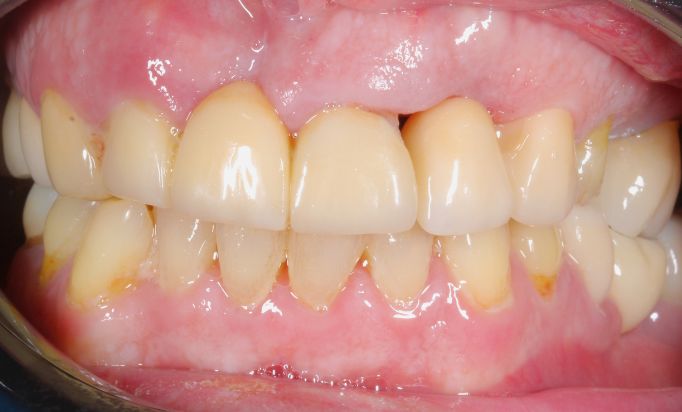

Periodontics

A secure, natural smile

Enjoy a radiant smile that reflects your personality.